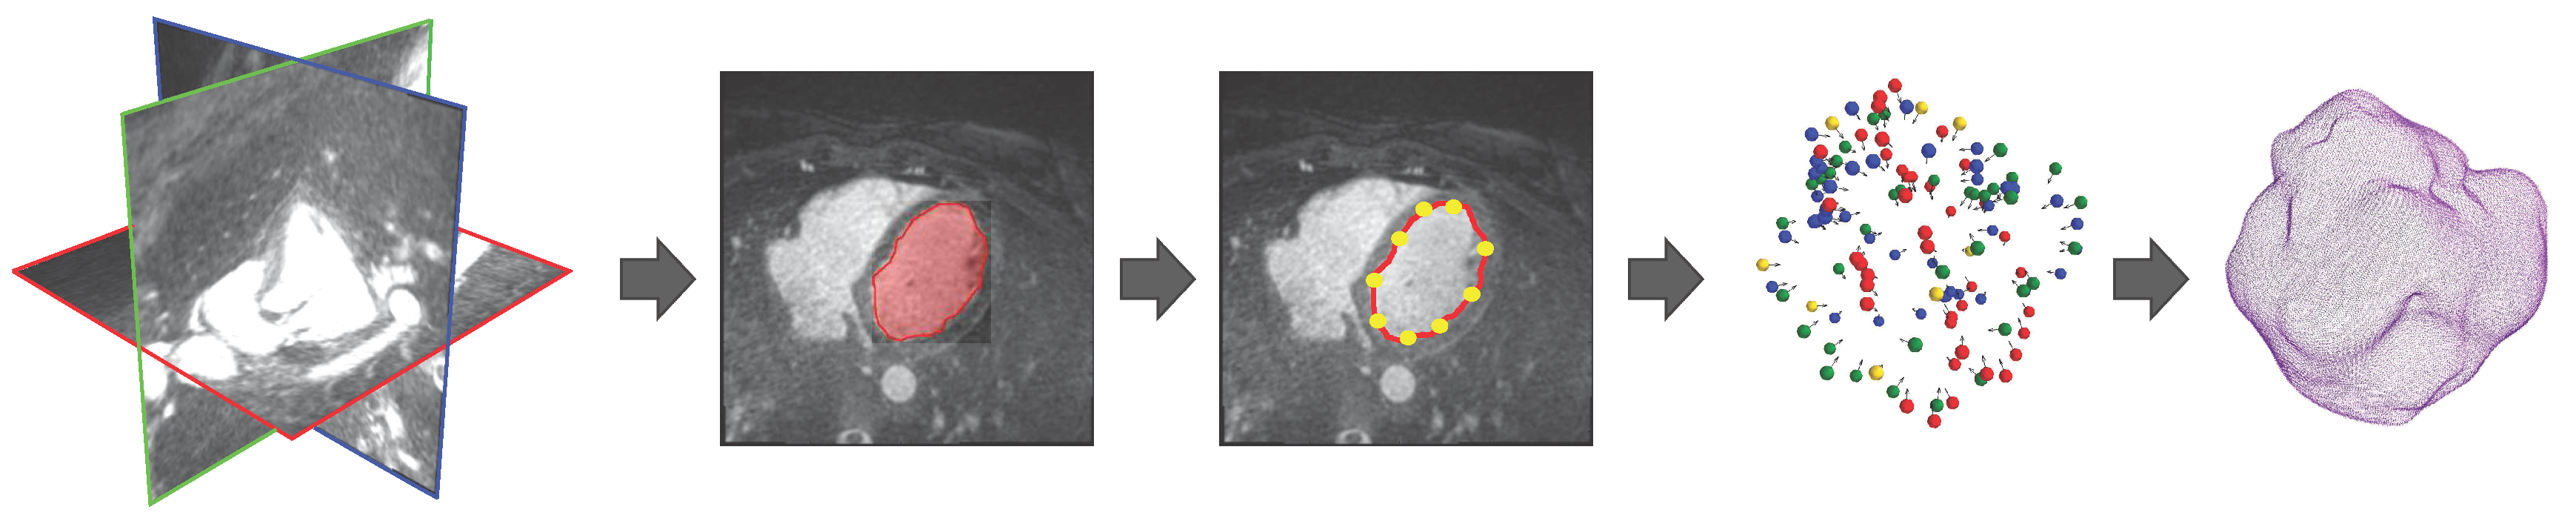

2. Methods

2.1. Smart Brush

2.2. Control Point Extraction

2.4. 3D Interpolation

2.5. Surface Reconstruction